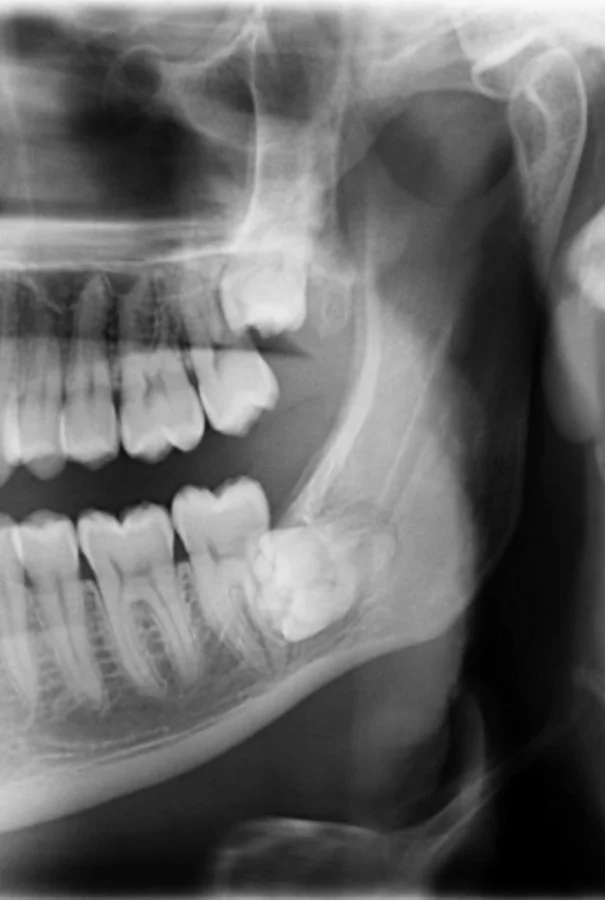

1. «В прошлом месяце я пришёл на чистку зубов к стоматологу. Я упомянул, что чувствую онемение в одном из зубов. Я был в ужасе, когда увидел опухоль, которая разрушает челюстную кость»